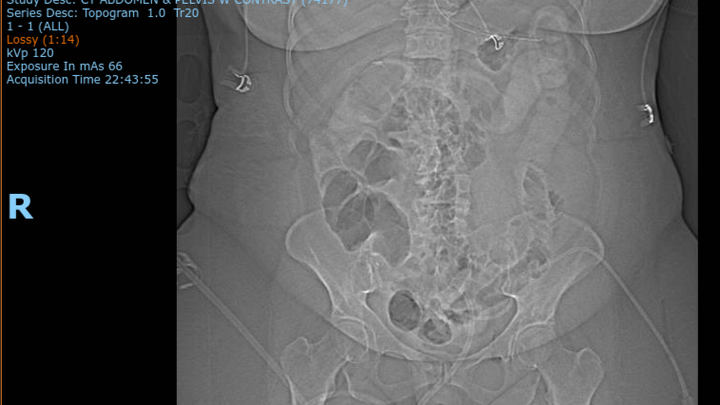

2-8-25: Returned to the ED for continued inability to have a bowel movement, increased pain, emesis after eating, and abdomen significantly more distended. More imaging and labs were again completed and with the results and consults to other doctors, the ED doctor determined it would best to transfer my mom to the U of I ED for further treatment. So she was transferred to the U of I where they then again did repeat labs and imaging. The fluid accumulation had again increased in size in her abdomen.

2-9-25: My mom was admitted to the U of I and had an Anterior Abdominal Fluid Collectioni drain placed. This allowed for them to not only removed 100’s of mL’s of fluid from her abdomen, but they were able to culture the fluid and with those results it was determined to no be urine, but bowel that had been sitting her abdomen for days. Increasing the infection and risks.

2-10-25: She remained at the U of I hospitals and underwent surgery on this day where they performed mesh explanation, bladder repair, abdominal wall washout, and apthra placement. Due to the increased amount of inflammation and inability to view the entire bowel, my moms abdomen was left open (that is what the apthra device was for) and she was moved to SNICU. She had an NG tube placed and was intubated and placed on a ventilator for the remainder of this day and into the next. Continuing to receive IV antibiotics with completion of MANY more tests and imaging.

2-11-25: She was extubated but remained in the SNICU for close monitoring due to her abdomen still being wide open and continued IV antibiotics. Plan at this time was to take her in for surgery the following day to close up her abdomen since contrast imaging completed on the 10th determined that there was no longer a leak in her bowel anywhere.